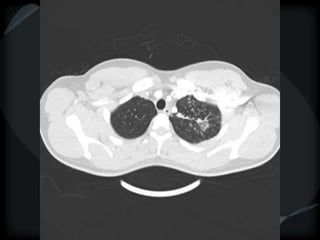

CT features of tuberculosis

 Cavity

 Transbronchial spread – tree-in-bud

 Transbronchial and hematogenous

Tuberculosis – TB spread

Tuberculoma – TB spread

Tuberculosis

bronchiolitis + hematogenous

TB bronchiolitis + hematogenous